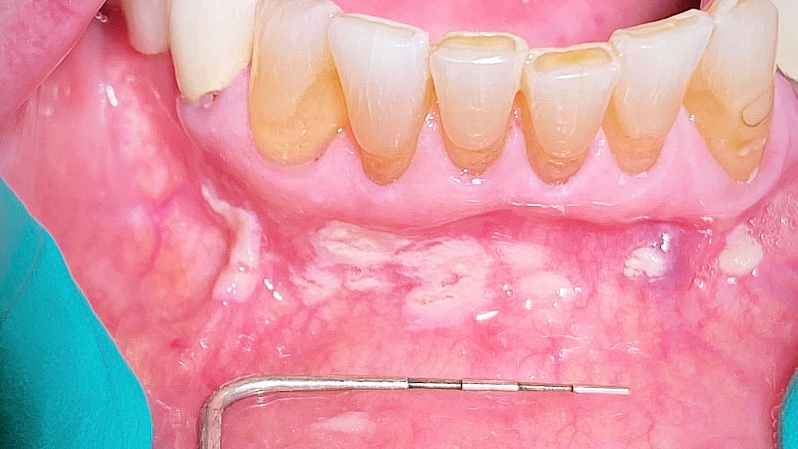

Clinical evaluation revealed scattered, white, creamy patches in the lower anterior vestibule, each measuring approximately 3–6 mm (figure 1). Now, take a look at the second picture after the white patches were easily wiped off with gauze (figure 2). Note the red, thin-membraned tissue? It was very tender to the touch and sensitive even to air.

This diagnosis should be a slam dunk—pseudomembranous candidiasis, aka thrush. Let’s have a refresher.

- Acute pseudomembranous candidiasis consists of creamy, loose patches of desquamative epithelium that are easily removed.1 Red tissue tender to the touch is what is painful to the patient.